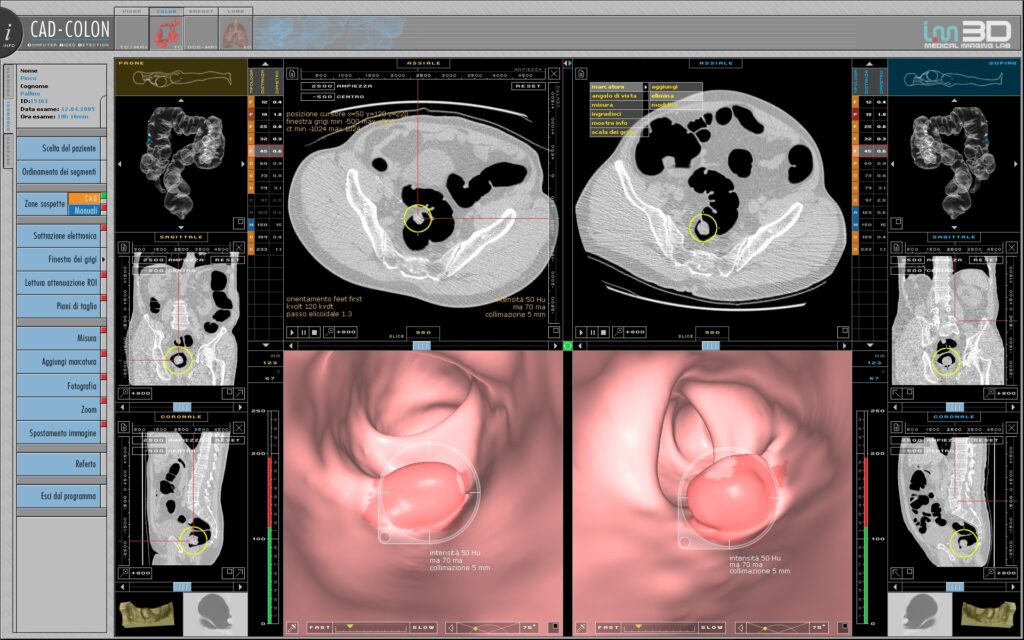

La colonscopia virtuale una tecnica di studio del colon-retto che utilizza dati ottenuti da un esame di tomografia computerizzata (o TAC), effettuato dopo aver introdotto aria nell’intestino tramite una piccola sonda rettale. Le immagini ottenute sono inviate ad una stazione di lavoro ed elaborate con software dedicato che consente di produrre immagini bi e tridimensionali dell’interfaccia mucosa-lume. Il radiologo ha la possibilità di osservare le ricostruzioni e di navigare virtualmente nel lume colico; i polipi ed i tumori sono riconosciuti in quanto sporgono nel lume intestinale o perché riducono l’ampiezza del lume e determinano un ispessimento delle pareti. Al contrario della colonscopia tradizionale, la colonscopia virtuale non richiede l’uso di un purgante ma di un semplice idratante delle feci; per essere preparato sufficiente che il paziente beva una piccola quantità di mezzo di contrasto a base di iodio prima dell’esame. Per questo motivo l’esame virtuale generalmente meglio accettato di quello tradizionale.